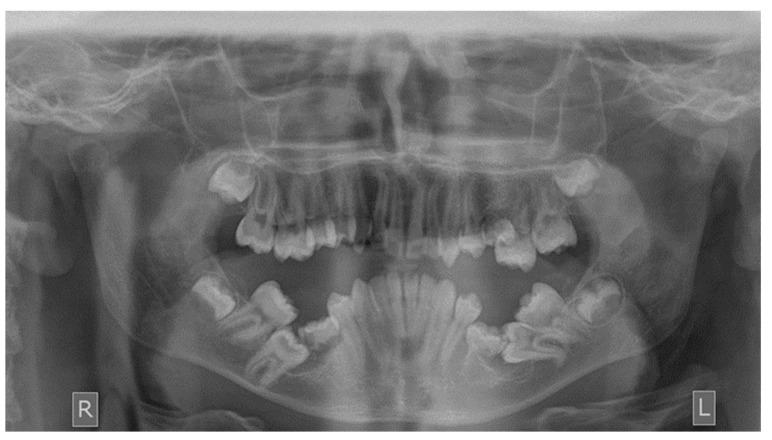

Panoramic radiographs of 1400 patients that sought orthodontic treatment in private practice were retrieved and examined. All teeth that had not been erupted at the time of the examination while their root formation was completed were considered impacted.

In total, 212 out of 1400 patients had at least one impacted tooth (15.14%). The highest incidence of tooth impaction was in the canines of the maxilla, followed by the central incisors of the maxilla, the second molars of the mandible and the second premolars of the mandible. The most common etiological factors responsible for the impaction were the ectopic eruption pathway, loss of space in the arch, the ankylosis of the deciduous teeth and the presence of supernumerary teeth.

方法

在1400名患者中,共有212名患者至少有一颗阻生牙(15.14%)。牙齿阻生的最高发生率在上颌尖牙,其次是上颌中切牙、下颌第二磨牙和下颌第二前磨牙。导致阻生的最常见病因是异位萌出道、牙弓间隙丧失、乳牙粘连和多生牙的存在。